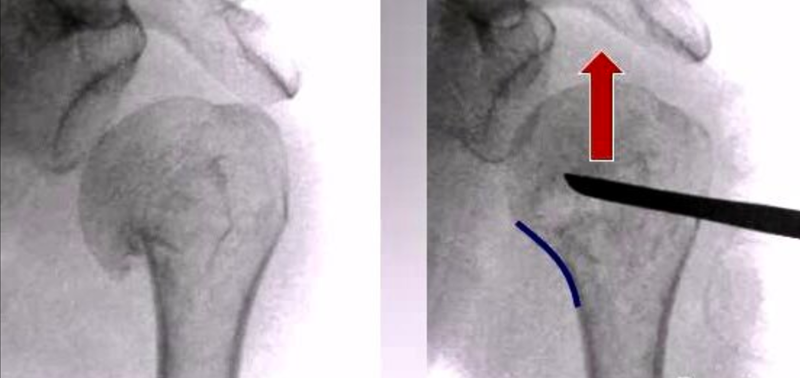

1、内翻压缩型二部分骨折闭合复位固定

(1)病理改变

肱骨干在内侧嵌插进入肱骨头,而外侧的骨膜完整,不会出现骨折分离。两个骨折块通常向前互相成角,完整的骨膜和骨折嵌插保留了一定的稳定性。

(2)复位固定技巧

肱骨干维持在轻度外展位轴向牵引,同时用大拇指在骨折部位成角处自前向后按压,以纠正骨折端向前成角。在复位过程中,必须确保两骨折端的内侧皮质尽可能的精确对位。

如果应用这种手法复位的方式不能将嵌插松解,则需要在骨折端下方5cm处纵形切一小口,置入一把骨膜起子,起子从肱骨干前方放入,紧贴皮质滑行,到达内侧肱骨骨皮质骨折端,维持上肢轻度外展并牵引,用起子将肱骨头翘起。

一旦完成以上步骤,在维持复位状态下,助手沿着预先已设定好的线路打入2.0mm克氏针2-3枚,即从骨折端以远打入直到针尖位于肱骨头的软骨下骨。